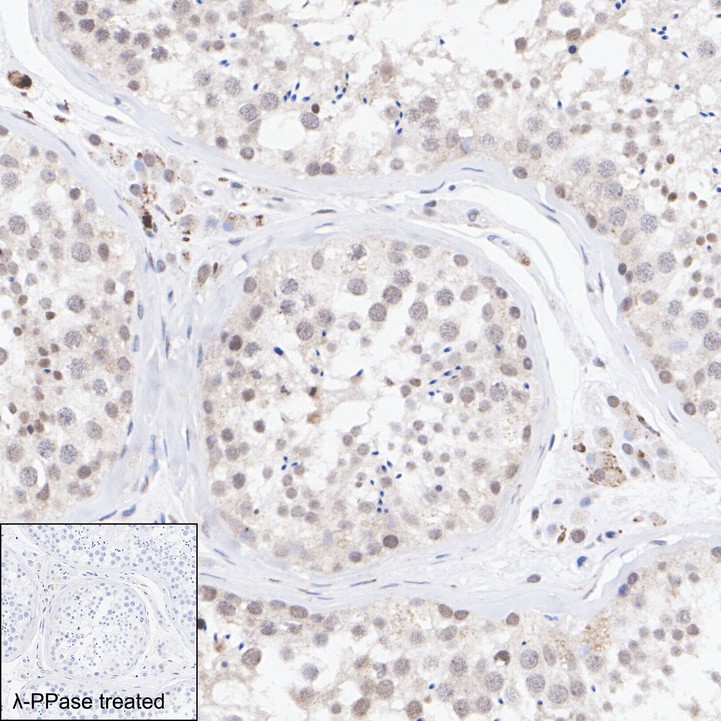

Phospho-IRF3 (S396) Recombinant Rabbit Monoclonal Antibody [PSH06-75] - BSA and Azide free

Catalog# HA751121

IHC-P